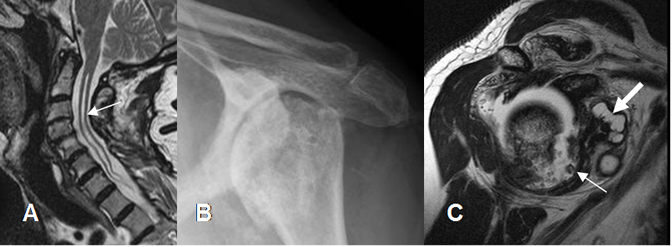

Alteración en la propiocepción por lesión de nervio periférico o de la medula osea, como la siringomelia.

Compromete ambos lados de la articulación, con un patrón hipertrófico (Esclerosis y formación de osteofitos) y otro atrófico (Osteopenia y reabsorción ósea). (Fig 164).

Fig 164. Artropatía neuropática.

A: RM sagital en T2. Cavidad de siringomelia en la medula cervical.

B: Rx AP de hombro. Signos de artropatía degenerativa, con pérdida del espacio articular.

C: RM sagital en T2. Sinovitis con algunos cuerpos libres (Flecha delgada) y líquido en la

bursa (Flecha gruesa).